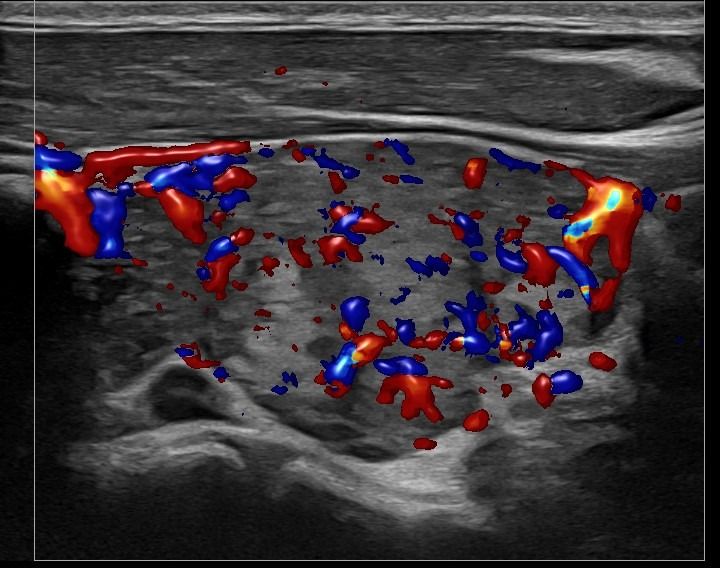

Με την τριπλή μελέτη του Θυρεοειδούς Αδένα, που περιλαμβάνει το B-Μode, το Έγχρωμο Υπερηχογράφημα και την Ελαστογραφία, γίνεται μια ολοκληρωμένη χαρτογράφηση του θυρεοειδούς αδένα. Το περίγραμμα, η αγγείωση και η ελαστικότητα του αδένα, καθώς και η υφή μίας πιθανής βλάβης αξιολογούνται με ακρίβεια και αξιοπιστία.